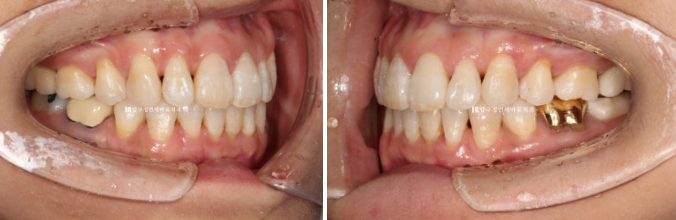

23.07~24.05

배열에서 가장 많이 벗어난 덕분에 잇몸이 유독 내려갔던 치아를 자세히 보겠습니다.

잇몸 퇴축이 회복이 되면서 치아뿌리 노출이 줄었습니다.